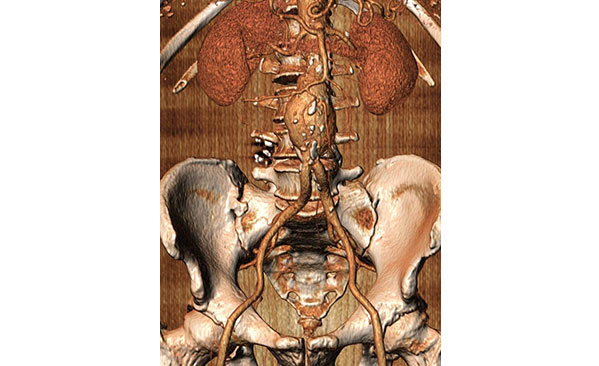

Άνδρας ασθενής 64 ετών με ανεύρυσμα κοιλιακής αορτής μέγιστης διαμέτρου 6,5 εκατοστών, χωρίς συμμετοχή των λαγονίων αρτηριών και με παρουσία βατών οσφυϊκών αρτηριών καθώς και κάτω μεσεντερίου αρτηρίας

Ενδαγγειακή αντιμετώπιση με την τεχνική της πλήρωσης του ανευρυσματικού σάκου με πολυμερές με χρήση των μοσχευμάτων Nellix, με σκοπό την αποφυγή ενδοδιαφυγής τύπου ΙΙ

Διαδερμική τοποθέτηση των μοσχευμάτων με βάση την καλή ποιότητα των μηριαίων αρτηριών, την κατάλληλη σωματοδομή του ασθενούς και την ιδιαίτερα χαμηλή διάμετρο της συσκευής εισαγωγής του μοσχεύματος